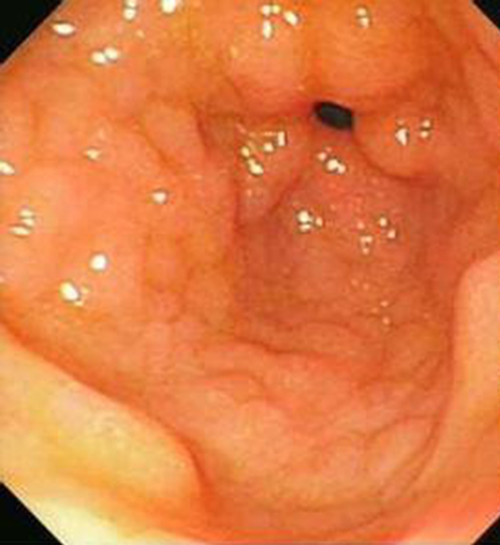

萎縮淺表性慢性胃炎